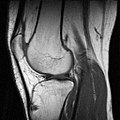

MRT-Kniegelenksaufnahme (sagittales Schnittbild) -

EIT des Brustkorbs (transversales Schnittbild) -